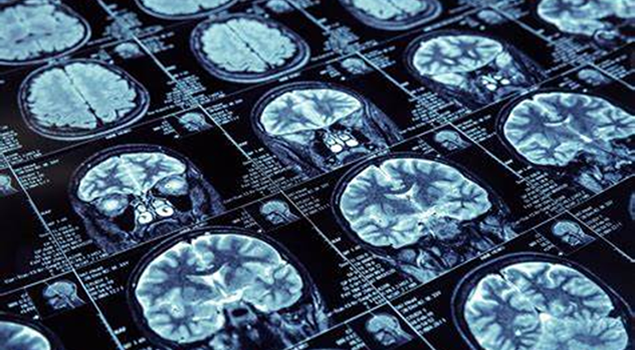

医生在可以通过视频会诊以及影像会诊的方式实现远程会诊,可以实现医学影像的远程传输和展示,方便医生进行远程会诊,提高了诊断的准确性和效率。

提高诊断的准确性和效率会诊系统的技术原理主要包括远程影像会诊系统的核心原理,即图像实时传输和专家远程参与。

区域影像中心建设让患者足不出户便可享受上级医院的远程影像诊断,不仅降低了基层医院的误诊/漏诊率,而且有利于提高影像医师的诊疗水平。